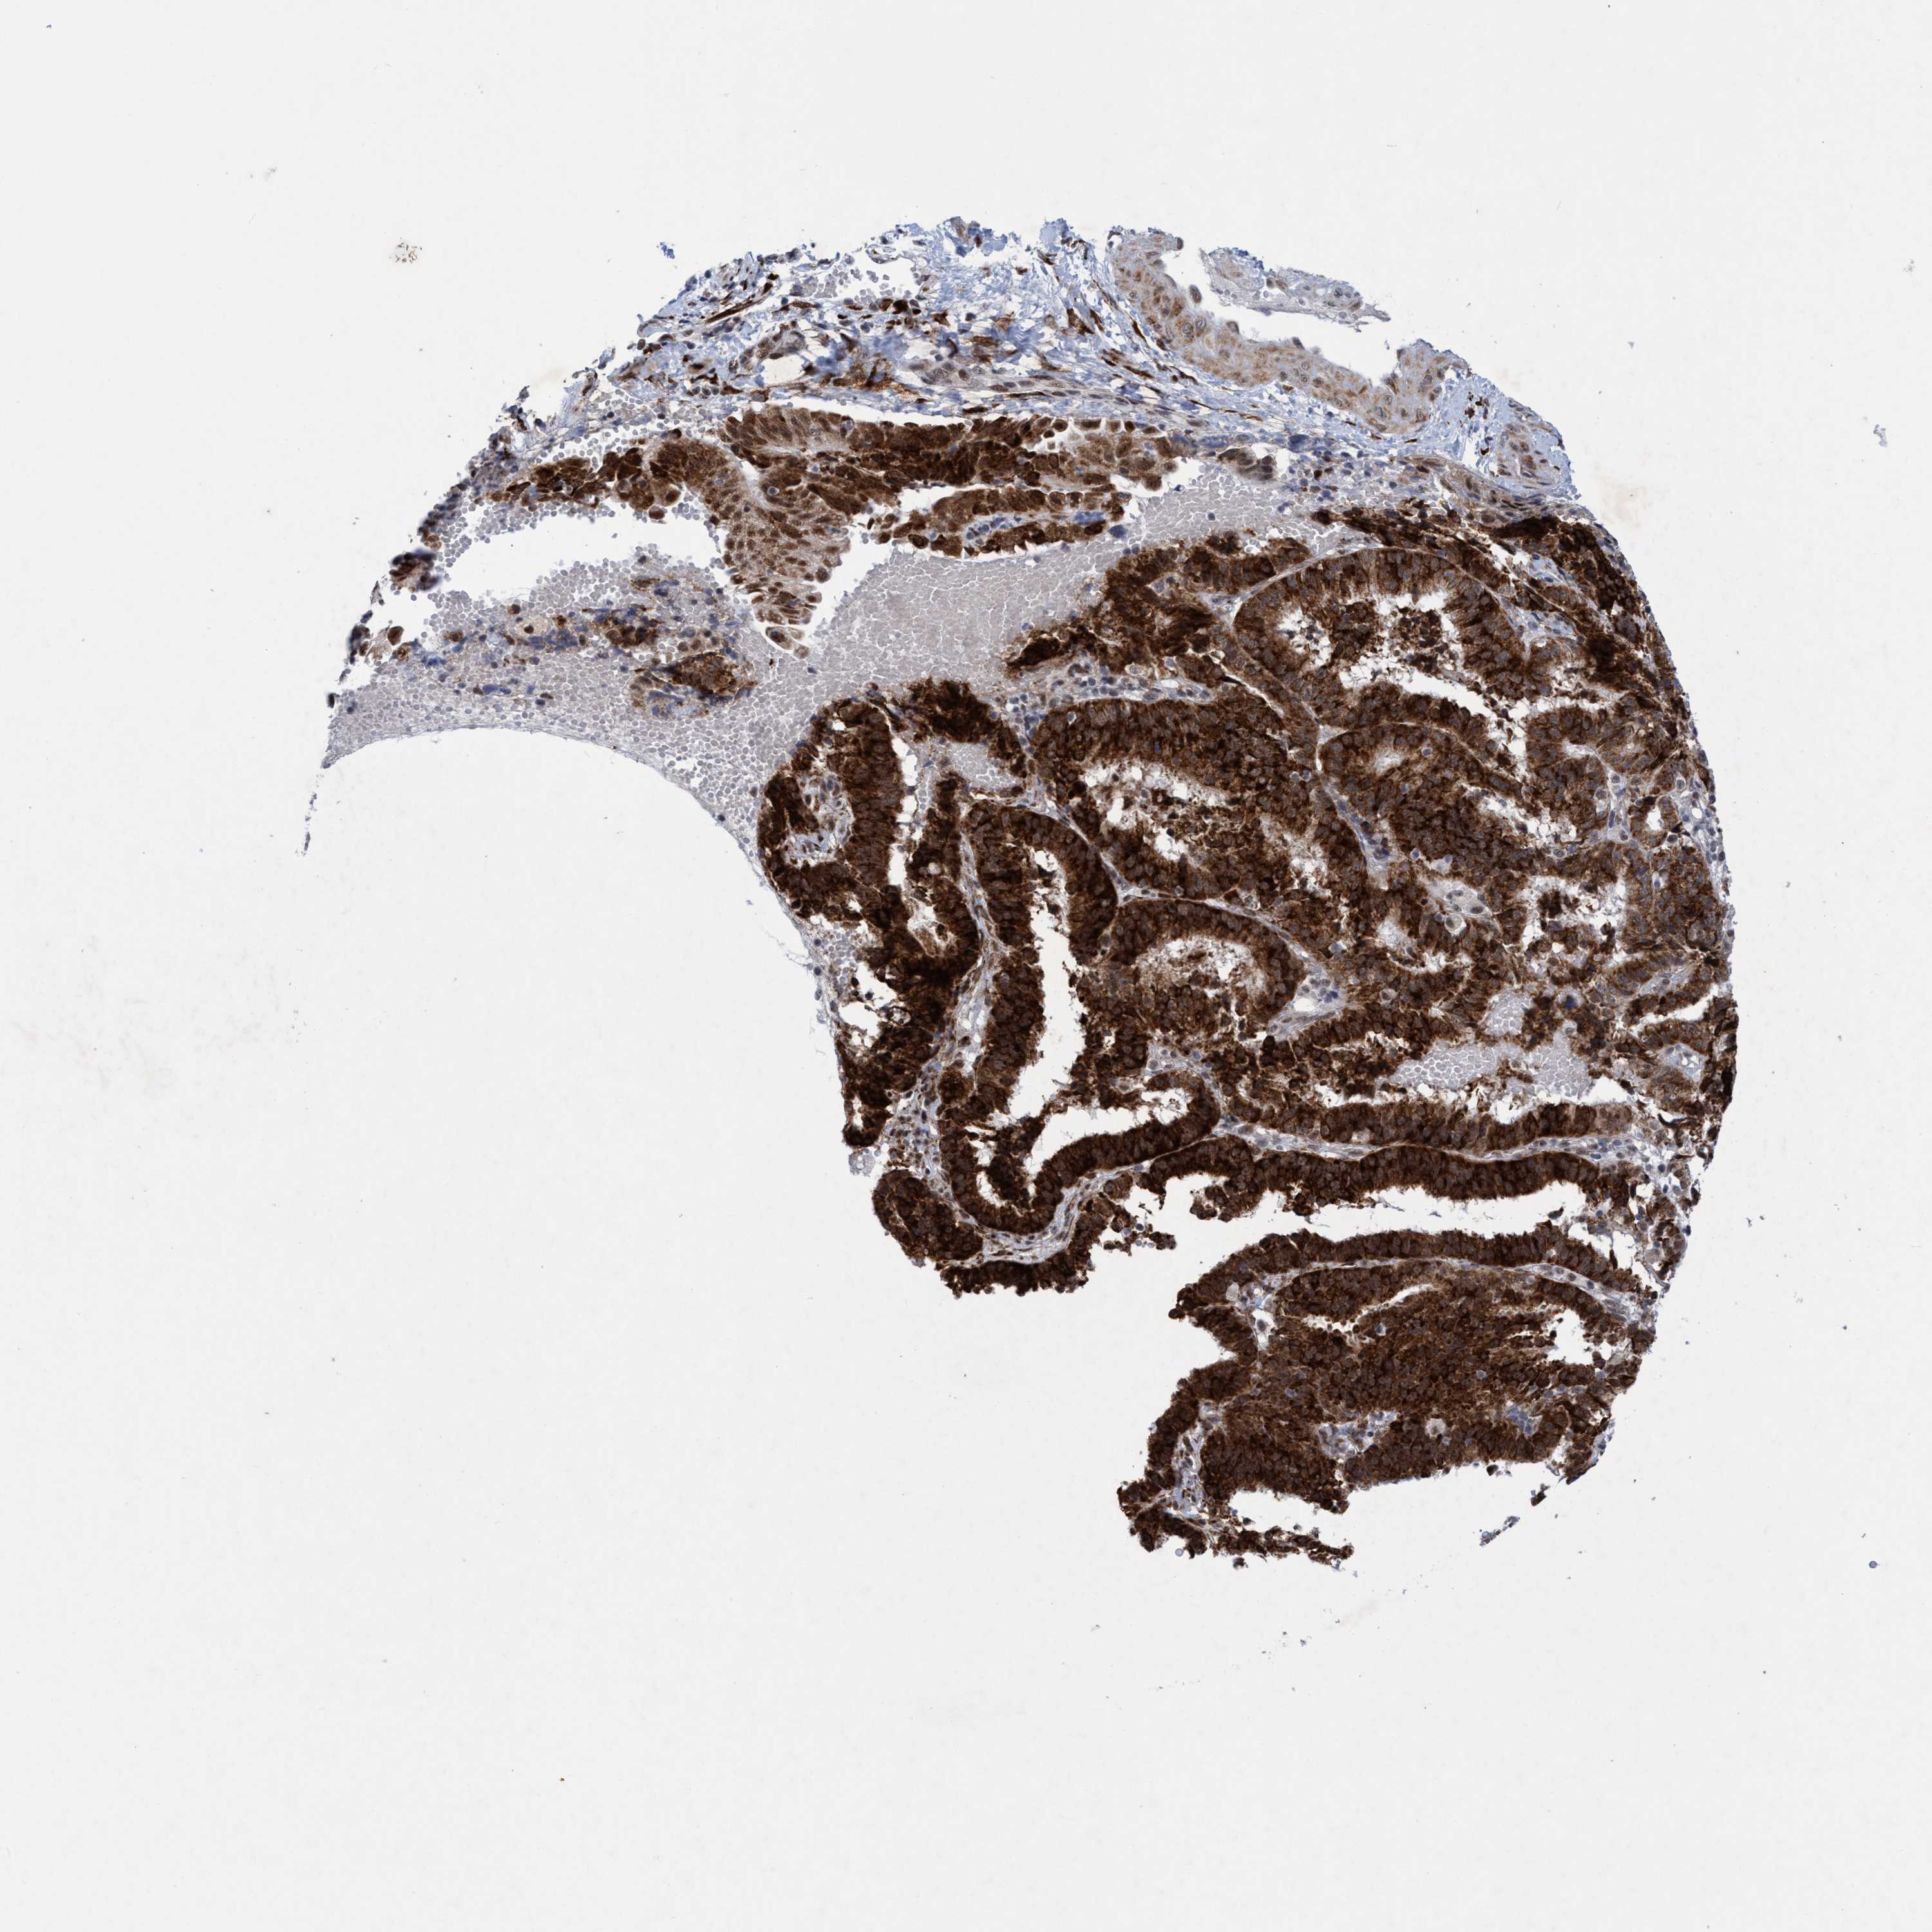

ENDOMETRIAL CANCER - Protein expressioni

A mouse-over function shows sample information and annotation data. Click on an image to view it in a full screen mode. Samples can be filtered based on level of antibody staining by selecting one or several of the following categories: high, medium, low and not detected. The assay and annotation is described here.

Note that samples used for immunohistochemistry by the Human Protein Atlas do not correspond to samples in the TCGA dataset.

Antibody stainingi

Antibody staining in the annotated cell types in the current human tissue is reported as not detected, low, medium, or high, based on conventional immunohistochemistry profiling in selected tissues. This score is based on the combination of the staining intensity and fraction of stained cells.

Each image is clickable and will lead to virtual microscopy that enables deeper exploration of all samples and also displays staining intensity scores, fraction scores and subcellular localization as well as patient and tissue information for each sample.

Antibody HPA023424

Staining

High

Medium

Low

Not detected

Intensity

Strong

Moderate

Weak

Negative

Quantity

>75%

75%-25%

<25%

None

Location

Nuclear

Cytoplasmic/membranous

Cytoplasmic/membranous,nuclear

Adenocarcinoma, NOS

Adenoma, NOS